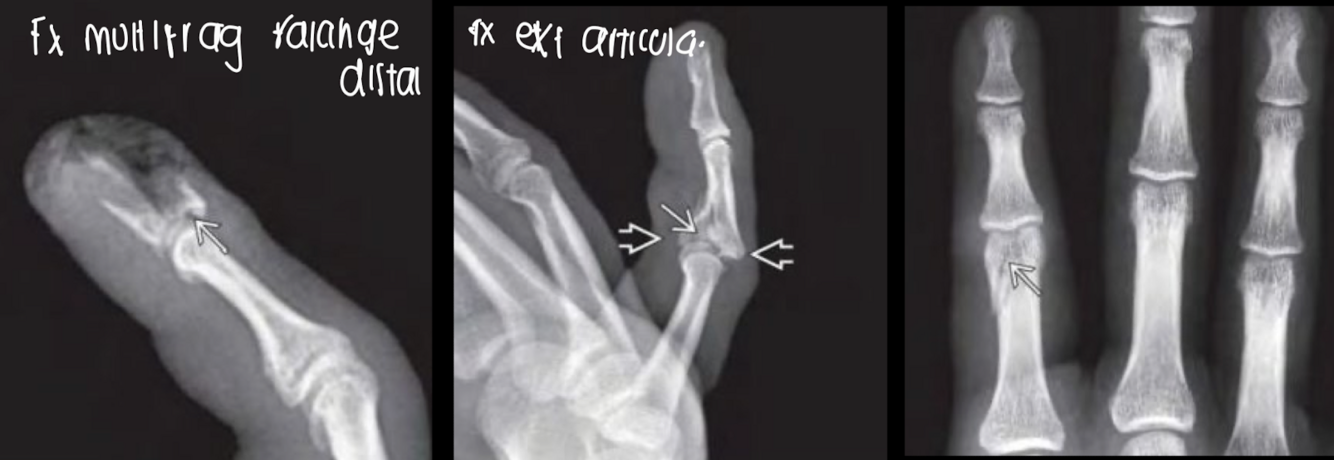

Fx de falanges

falanges AP Y LAT DE 1 DEDO

metacarpianos AP Y OBLICUA MAS DEDOS

Fx falanges RX